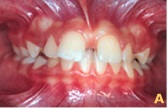

Ainda o caso 1

Já os casos patológicos, com disturbios imediatos e de certa gravidade, exigem intervenção imediata do profissional, independente do estágio de desenvolvimento do paciente.

Neste contexto, considera-se a divergência do longo eixo das coroas dos incisivos centrais, problemas periodontais decorrentes da impacção alimentar, dificuldade de higienização, a estética e o desenvolvimento de hábitos bucais deletérios como quesitos que mereciam atenção imediata.